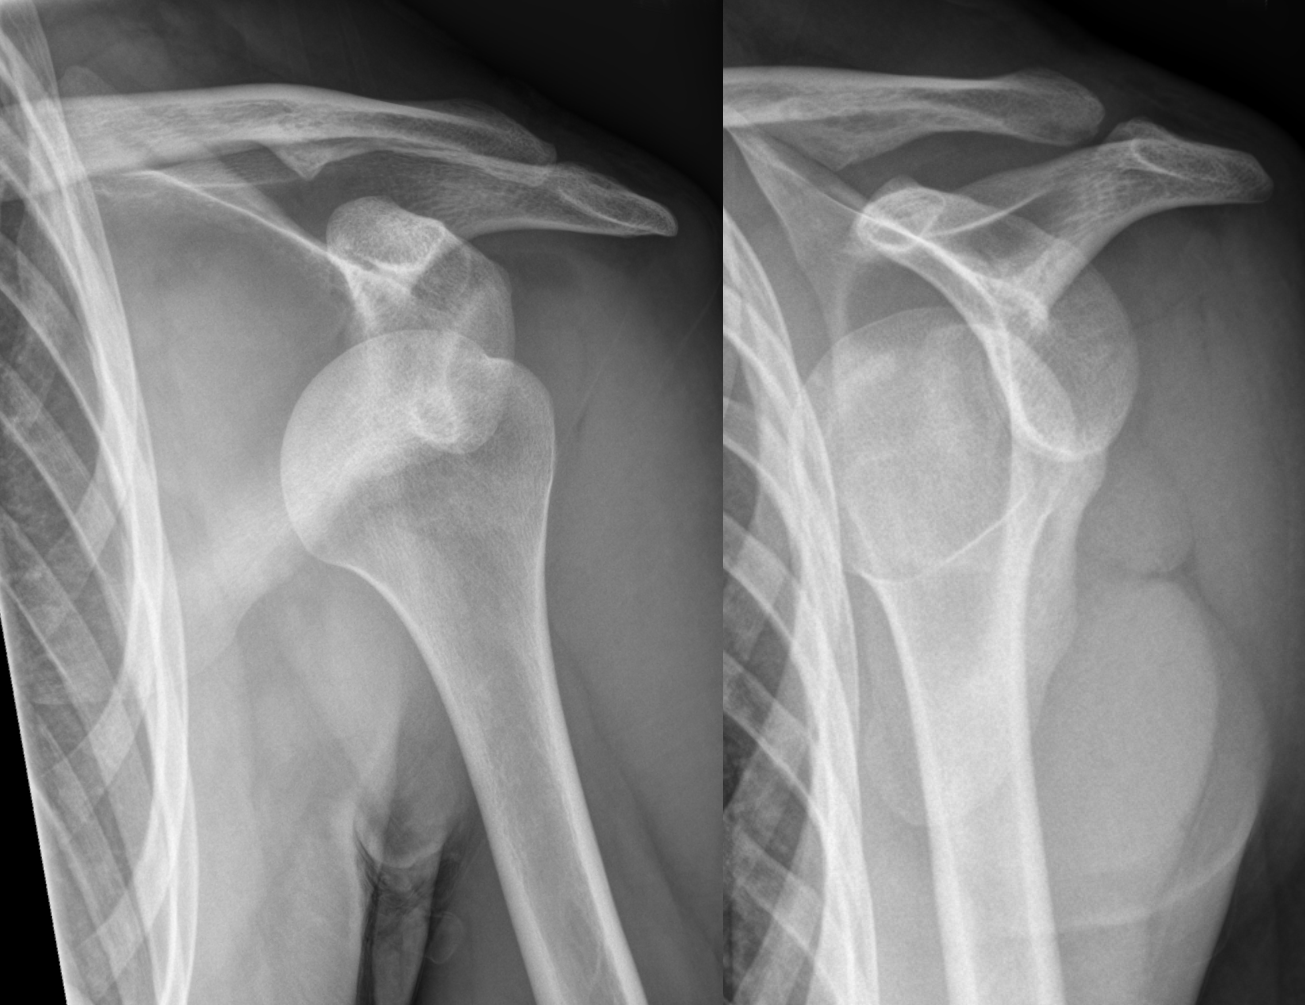

Diagnose this injury. Provide Moi, signs and symptomsand management

glenohumeral disclocation

moi - anterior = abduction , external rotation and extension, inferior, posterior = abduction, internal rotation

signs and symptoms = flattened deltoid contour, inability to move arm, moderate - severe pain, nerve involvement - numbness/ tingling

management - do not relocate - damage to nerve and blood vessels, immobilise with sling, police, refer to medical professional to relocate, use protective gear /braces , restore ROM, stregthen, prevent reoccurence